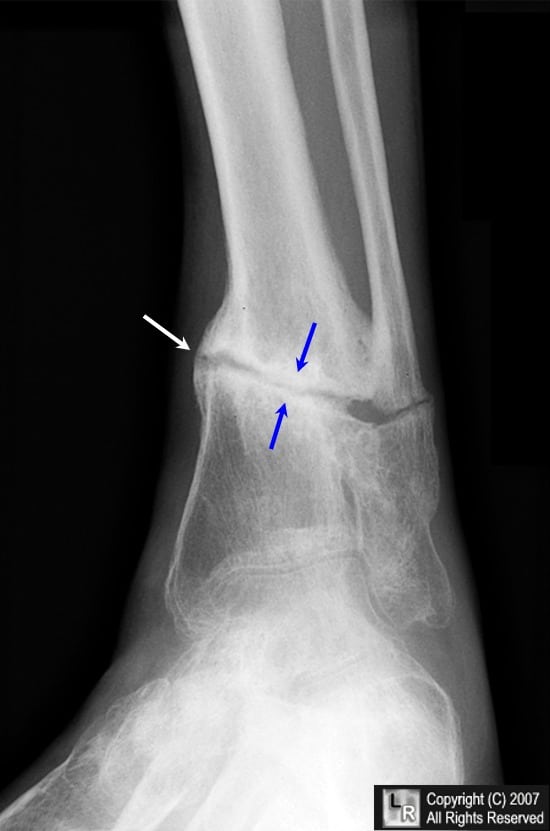

Если выразиться проще, псевдоартроз – это патологический сустав, возникший в том месте, где его быть не должно. К примеру, он может сформироваться в теле большеберцовой кости и привести к аномальной подвижности ее фрагментов. На рентгенограммах можно увидеть четкую щель между отломками и полное закрытие костномозговых каналов замыкательными пластинками.

Поставить диагноз «псевдоартроз» врачи могут не ранее, чем через 6-8 месяцев после перелома. Для этого им достаточно проанализировать результаты рентгенологического исследования.

В большинстве случаев врачи диагностируют псевдоартроз без особых трудностей. Если у них появляются сомнения или возникает потребность в уточнении характера дефекта, они назначают дополнительные методы исследования. Чаще всего пациентам делают рентгенографию или компьютерную томографию.